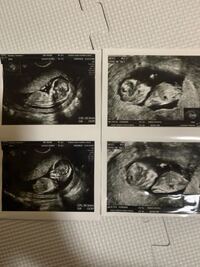

妊娠週 11w3d 今日の赤ちゃんです! 二人目妊娠で11週3日です。 流産経験ありで5センチの子宮筋腫持ちの為まだまだ不安ですが1日1日大切に大事に育てたいと思います。 6週辺りから全く出血も腹痛もなく今日の検診では赤ちゃんは既に5㎝に! ! エコーでも可愛くて愛しく携帯の待ち受けにしました。 お腹に宿った新しい命&長女宝物です。 パパにもこの気持ちJul 12, 16 · 妊娠14週目は、ママと赤ちゃんをしっかりと繋いでくれる胎盤が完成する一歩手前となりました。この頃には誰が見ても妊婦と分かるほどママのお腹は膨らみが目立つようになり、以前まであったウエストのくびれともしばしのお別れとなるよDec 06, 19 · 妊娠11週。 「まさか、と頭が真っ白になった」。 2週間後に絨毛(じゅうもう)検査を受け、赤ちゃんは ダウン症 と診断された。 検査前は